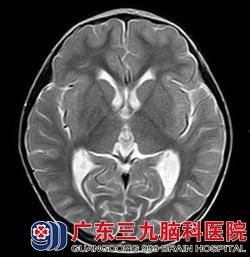

经华刚医生详细询问病史及查体后,明确患儿目前左侧小脑半球存在占位性病变。根据患者年龄结合头颅磁共振,考虑髓母细胞瘤可能性大,且病变已形成小脑扁桃体下疝,体征上已有不能走一字步,指鼻不准确、双手快速轮替运动差等症状。若肿瘤进一步生长,患者上述功能将进一步变差,甚至肿瘤严重压迫脑干,造成心跳呼吸骤停等风险。另外,因脑脊液循环通路因受肿瘤压迫,脑室内的脑脊液不能按正常途径回流,造成脑室内脑脊液过多、渗出,常常出现胡言乱语、大小便失禁、呕吐、精神反应变差等症状。患者需尽快行手术治疗,否则后果不堪设想。

看着生病的女儿情况一天比一天糟,小茹的父母心如刀割,但几万元的手术费用对一个务农的家庭来说是笔大数目。是放弃还是手术,小茹的父母内心苦苦挣扎着。在亲戚朋友劝说及帮助下,小茹父母终于筹到手术费用,为小茹办理了入院手续。接下来,医生们为小茹进行了“左侧小脑占位病变切除术+右额脑室外钻孔引流术”,术程顺利。术后病理示:髓母细胞瘤 WHO IV级。